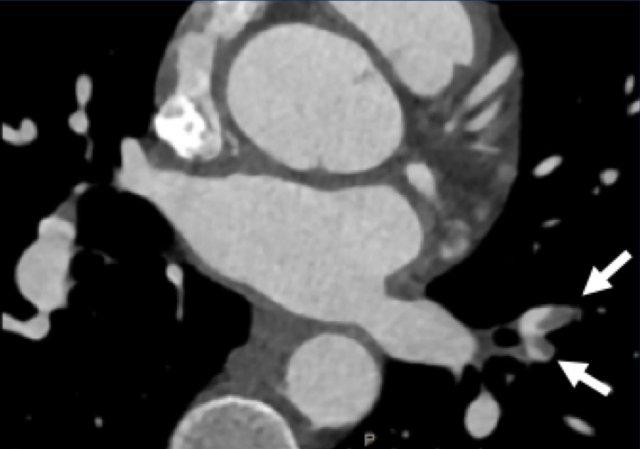

Of patients presenting with acute chest pain 5-10% suffer from STEMI,

Non-cardiac conditions include acute aortic syndrome (e.g. intramural hematoma,

penetrating atherosclerotic ulcer, dissection or rupture), pulmonary embolism

(see arrows in figure), pericarditis, or other intra-thoracic pathologies.

Image

Multiple pulmonary emboli (arrows).